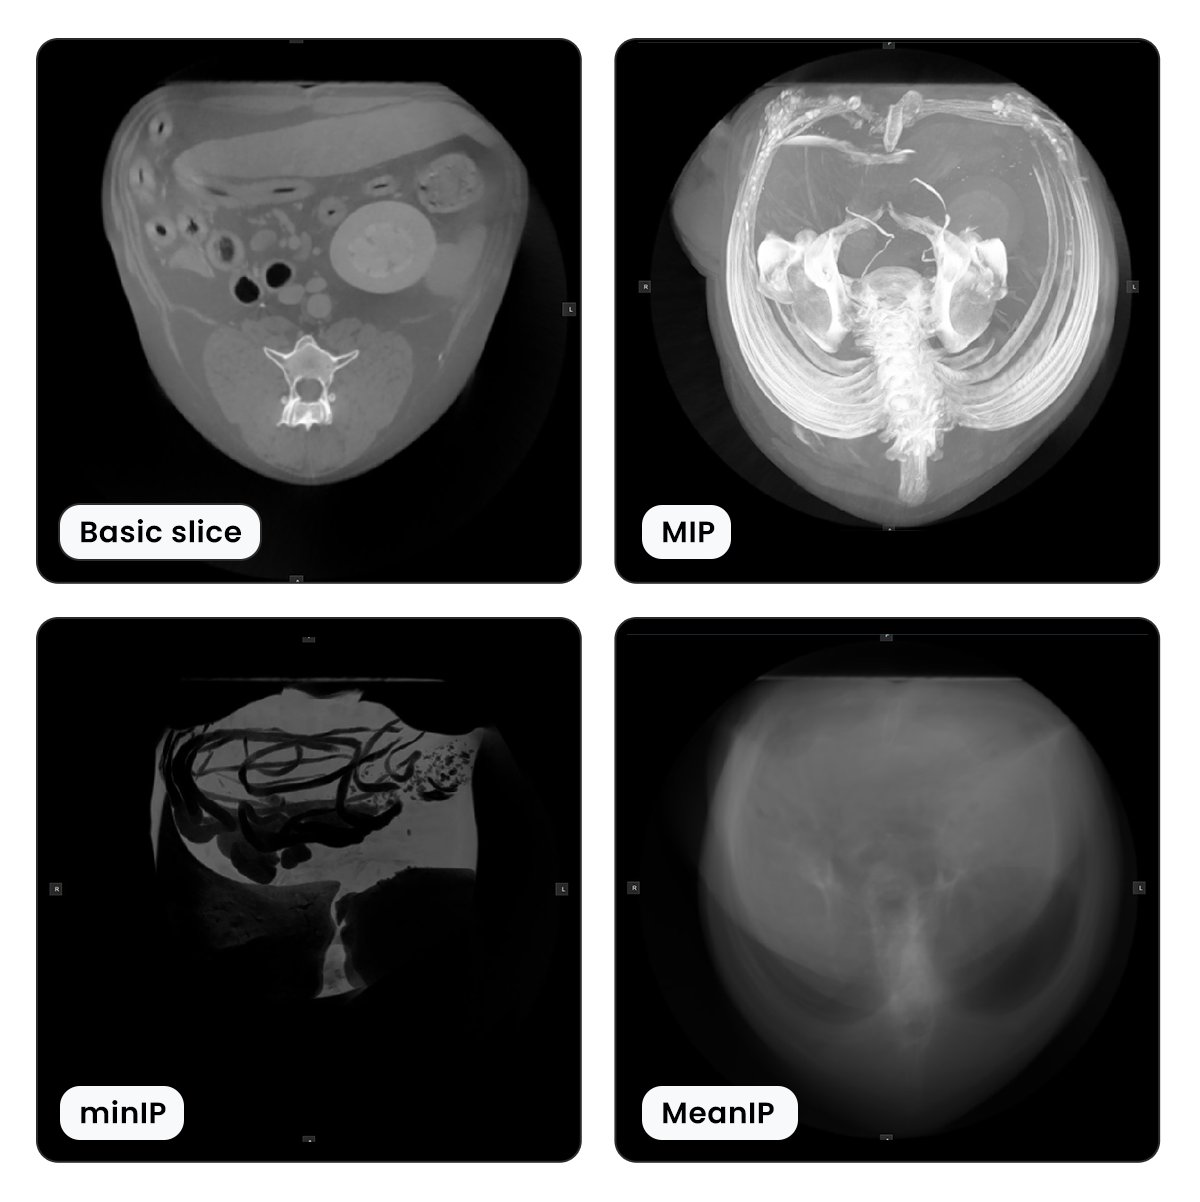

Thick Slab and Rendering Modes¶

The 3D relationship of the structures in the body can sometimes be better understood by seeing multiple slices simultaneously. For this purpose, the VisioVIEW CT Viewer offers users the ability to choose the specific Thick Slab mode, changing the way the slices are represented in the view.

Types of Thick Slab Rendering Modes¶

There are three different thick slab rendering modes available for viewing multiple slices in one view simultaneously.

MIP - Maximum Intensity Projection: Displays the highest intensity value of each voxel from the available slices.

MinIP - Minimum Intensity Projection: Displays the lowest intensity value of each voxel from the available slices.

Mean Intensity Projection: Displays the mean average value of each voxel from the available slices.